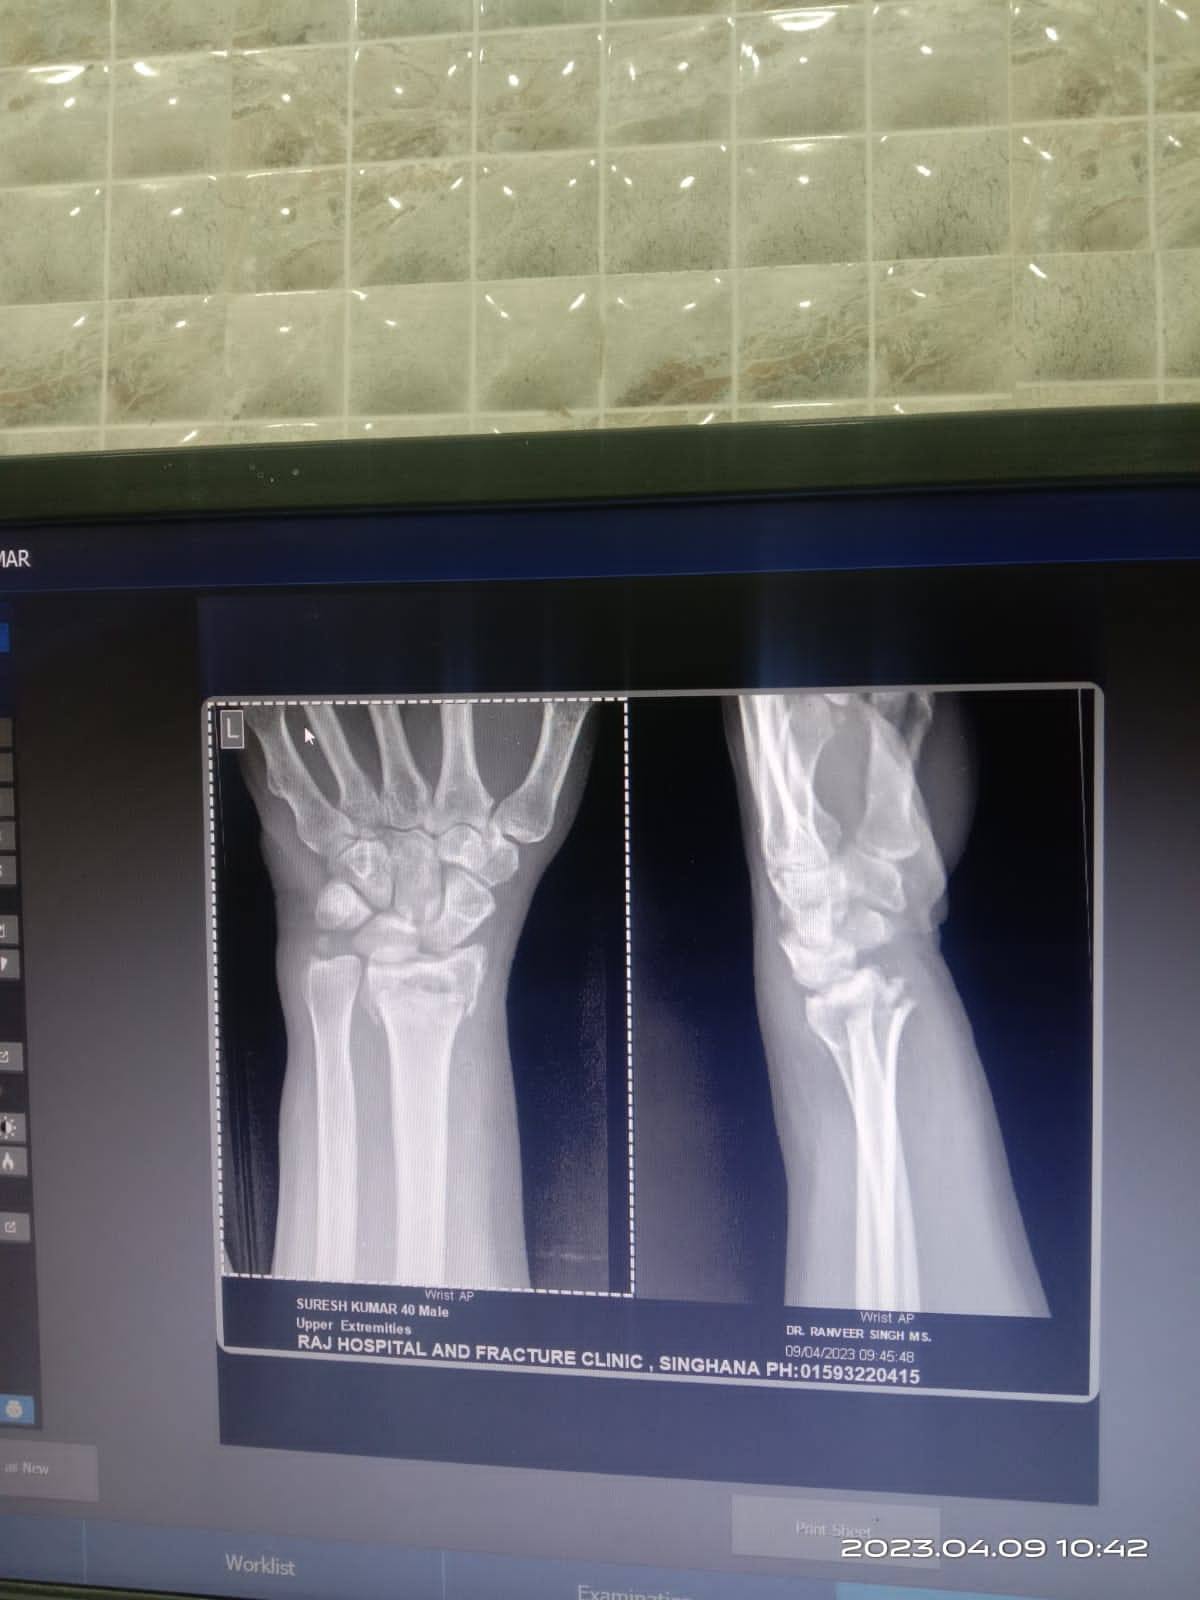

Kunal Gahalawat

गिरने से कलाई में फ्रैक्चर h opretion karwana होगा या पलस्तोर से ठीक हो जायेगा